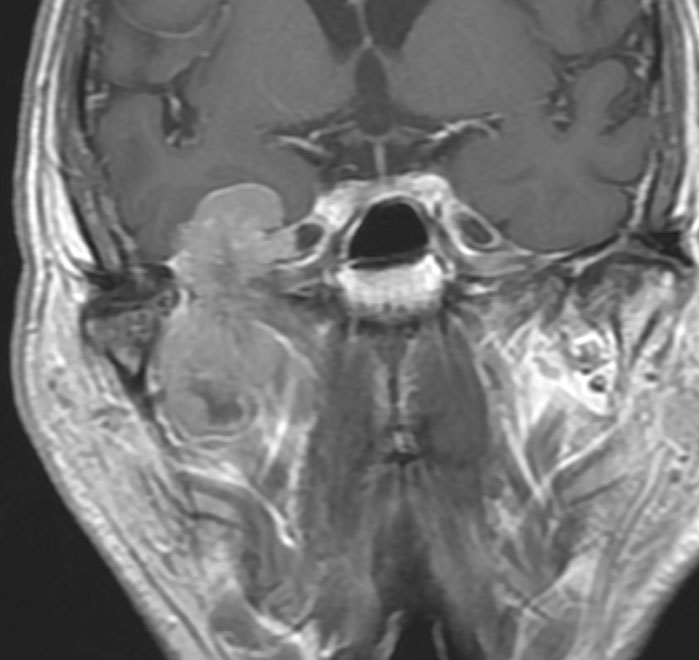

静脈洞交会 confluence に浸潤しているものです。直静脈洞は閉塞しています。右のMRIでは,ガドリニウム増強像が強弱まばらになっています。髄膜腫と診断したいのですが,ちょっと何かが違うというのがSFTです。硬膜や骨や脳に浸潤性格を有します。亜全摘出して術後に54グレイの放射線治療をしました。

5年後に小脳内に再発しました。全摘出したのですが,その後もあちこちに再発を繰り返しています。最初はグレード2でしたが,再発を繰り返すと増大速度が速くなり,再発までの期間が短くなり,多発性再発となってきます。